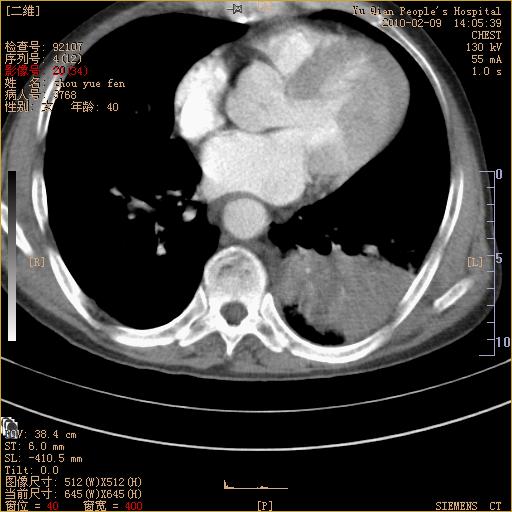

男性,73岁,咳嗽咳血数天,诊为肺ca伴左肺下叶后段阻塞性炎症、肺不张妥否?

左下肺中央型肺癌伴结段形肺不张,左侧胸腔积液,纵隔内见部分增大淋巴结(反应性增生或转移)

左下基底干支气管明显变窄。

左肺下叶基底段支气管狭窄,左肺门增大,左肺下叶团片状病灶。中心型肺癌伴柱塞性炎症可能大,建议支气管镜检查。

左下肺中央型肺癌伴节段性肺不张,左侧胸腔积液,纵隔内见肿大淋巴结

左下基底段支气管变窄。建议进一步纤支镜检查。

1、左肺下叶后基地段肺癌伴阻塞性炎症,左下肺门淋巴结转移。2、左侧胸腔积液。